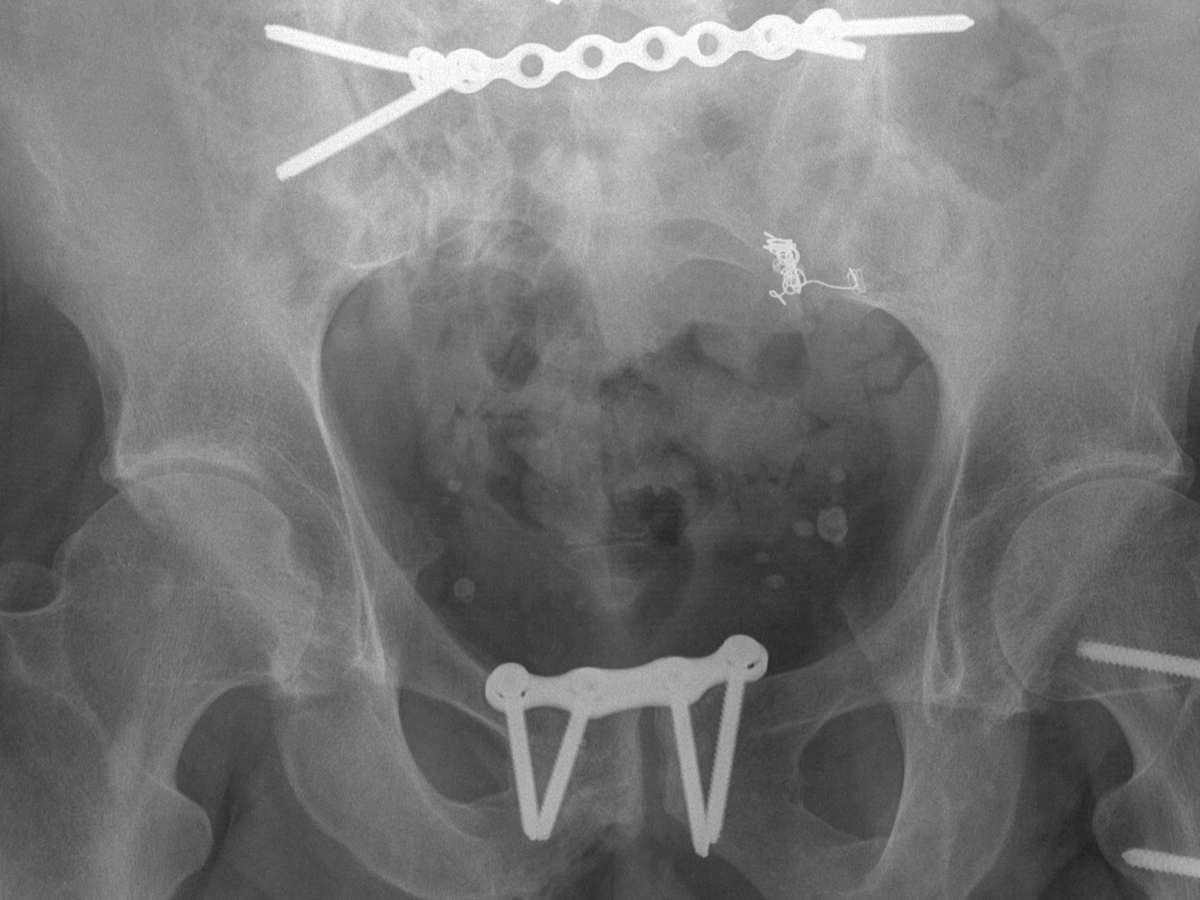

My name is Mark and after a near fatal car accident I was left with poor circulation in my legs due to an 'open book' fracture of my pelvis and femur. Due to the poor circulation I developed leg ulcers some years ago and these have refused to heal, due in large part to my weight. I have been in compression bandaging for nigh on 3 years but healing has been minimal. This is despite twice weekly appointments and dressing changes.